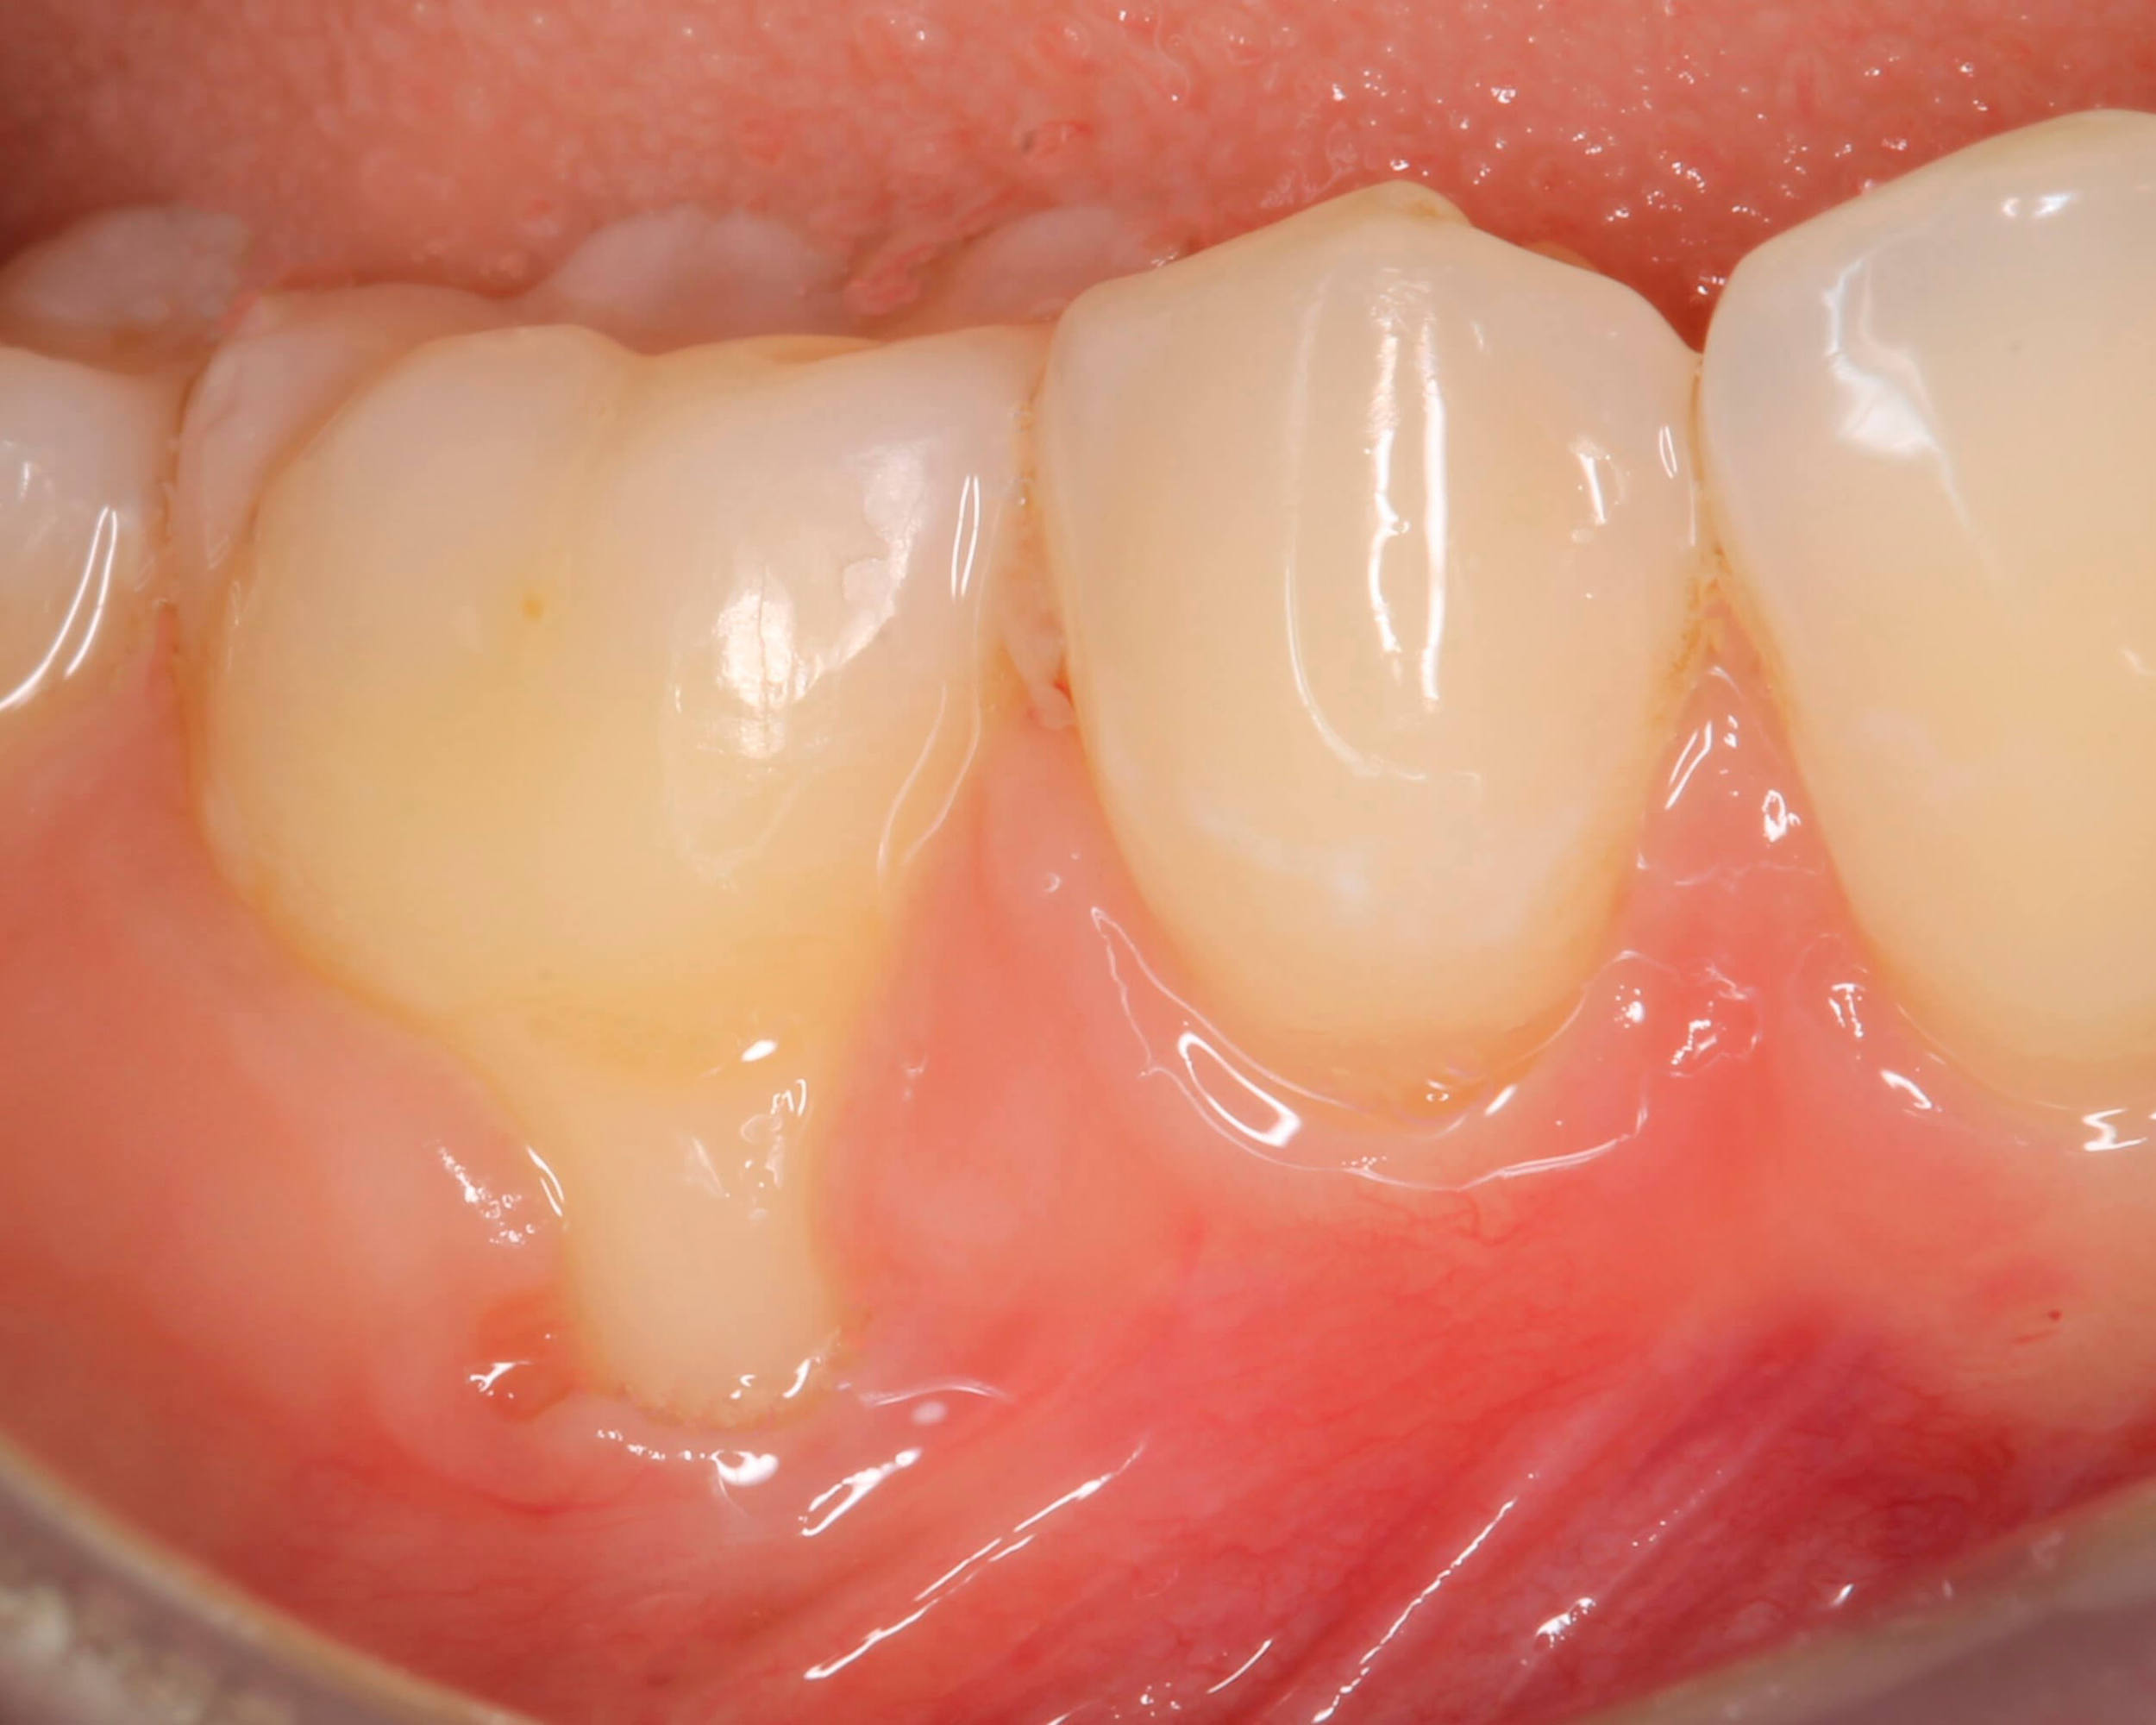

Enrojecimiento de la encía

Es importante que la persona se acostumbre a observar las distintas partes de la boca y la lengua para que pueda notar los cambios que ocurren y tomar medidas antes de que sean padecimientos serios. Si nota que la parte de la encía que rodea los dientes se enrojece, aun cuando no duela ni sangre todavía, debe consultar con el especialista.

Sangrado de la encía

muchas personas les sangra la encía cuando se cepillan los dientes, y creen que es normal que suceda, pero no es así. Cuando las encías sangran, es el síntoma de que tiene un problema de gingivitis. Si la enfermedad no se trata, el sangrado puede progresar en intensidad y frecuencia, y convertirse en un problema.

Inflamación de la encía

La inflamación de la encía es otro síntoma de gingivitis que debe tratarse.